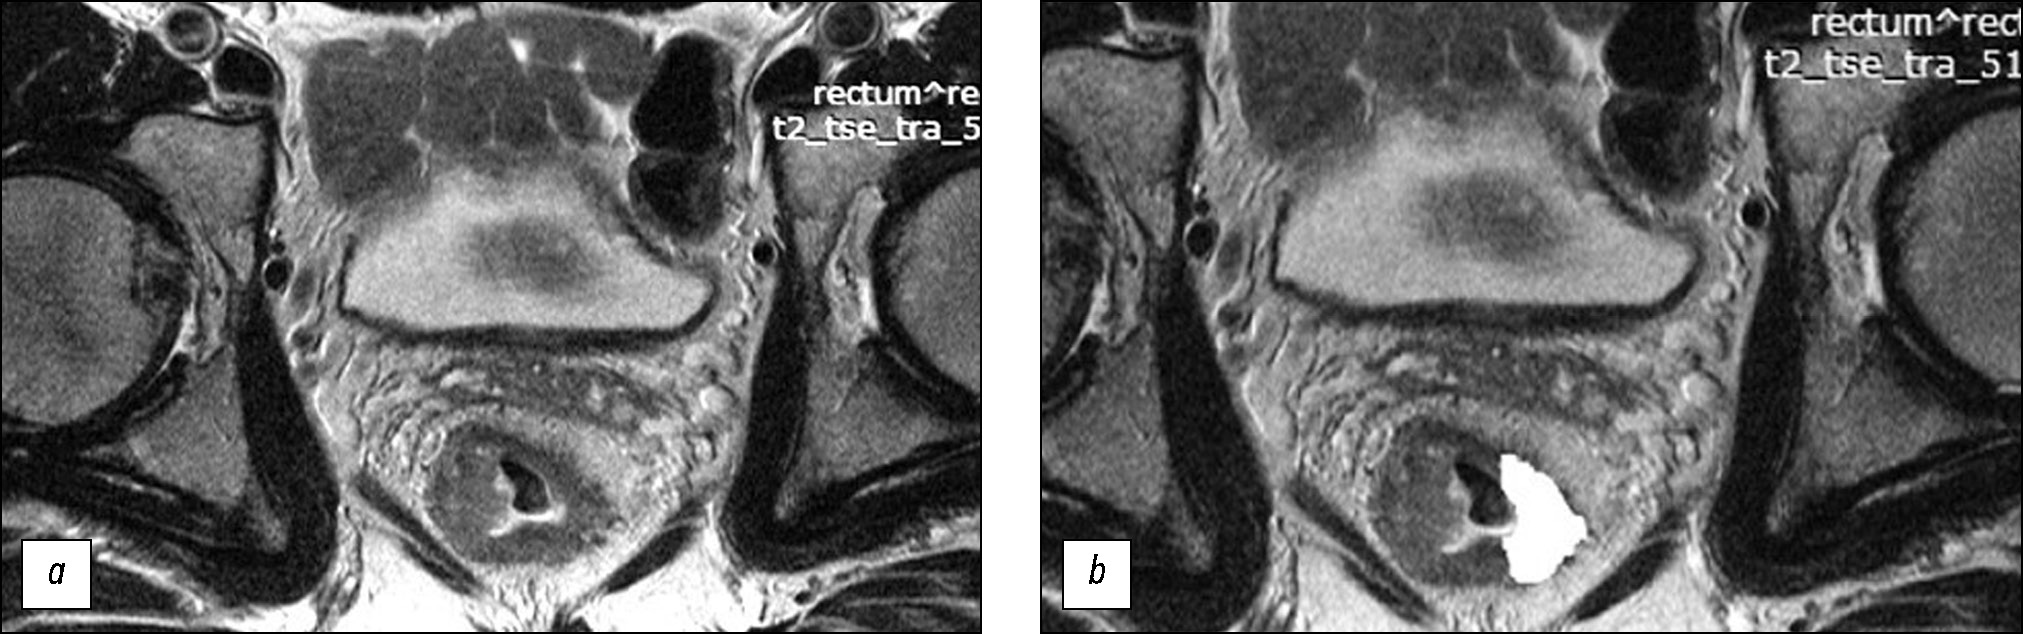

MATERIALS AND METHODS: The retrospective study enrolled 82 patients with locally advanced rectal cancer who received combination treatment with neoadjuvant chemoradiotherapy. Patient data were divided into the training (n=58) and control (n=24) sets. For texture analysis, primary high-resolution T2-WI at the level of the tumor center, oriented perpendicular to the intestinal wall, was used. The texture analysis was performed by second-order statistics based on the gray-level co-occurrence matrices using MAZDA ver. 4.6 featuring the calculation of 11 texture parameters. In the training set, based on the morphological assessment of surgical specimens, significantly different texture analysis parameters were found for two groups of patients: neoadjuvant chemoradiotherapy responders (good prognosis group) and nonresponders (poor prognosis group). Accordingly, a scoring system was created for assessing the efficacy of neoadjuvant chemoradiotherapy. The system was tested on the control set, and diagnostic efficacy parameters were determined.